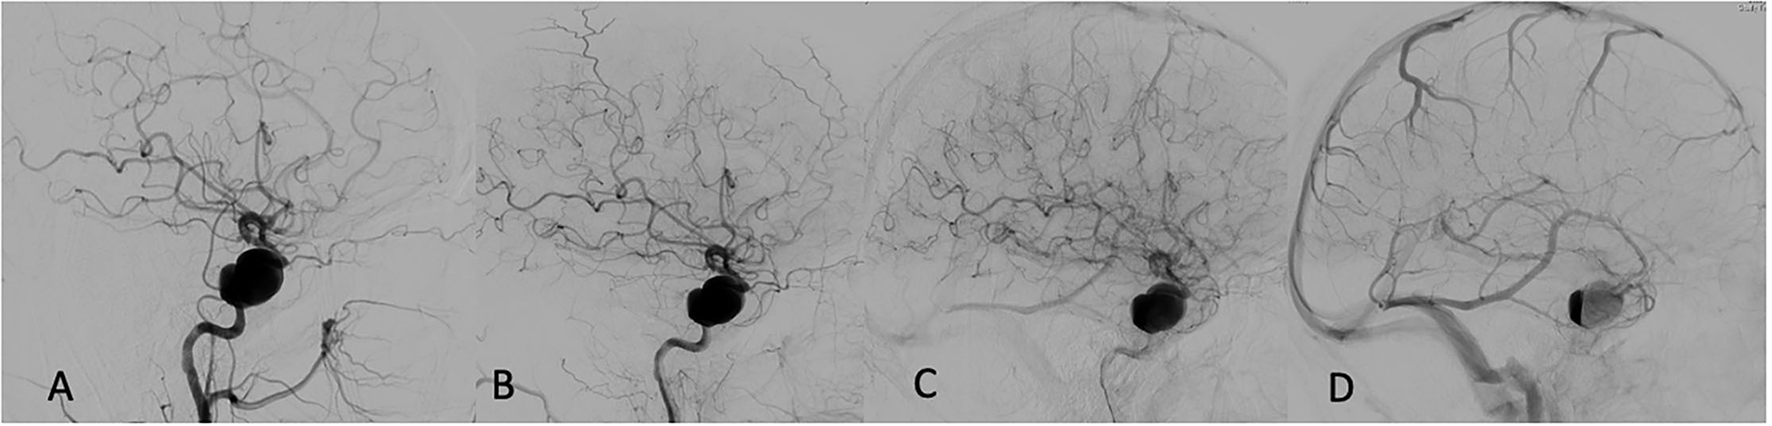

Multivariate regression analysis revealed that among all analyzed variables, such as aneurysm size (p = 0.99), device type used (p = 0.69), age (p = 0.87), appearance of the eclipse sign pre-and post-FD (0.93), the most reliable predictor of permanent aneurysm occlusion at 12 months was prolonged and sustained eclipse sign visibility in more than three angiographic phases (p < 0.001). An example of a patient with a successfully treated large aneurysm and visible pre-intervention eclipse sign with significantly prolonged and delayed appearance post-FD embolization is depicted in Figure 1.

FIGURE 1

Figure 1. Pre-embolization angiogram: (A) Early arterial phase. (B) Late arterial phase. (C) Capillary phase. (D) Venous phase—first appearance of eclipse sign prior to flow diversion (FD).